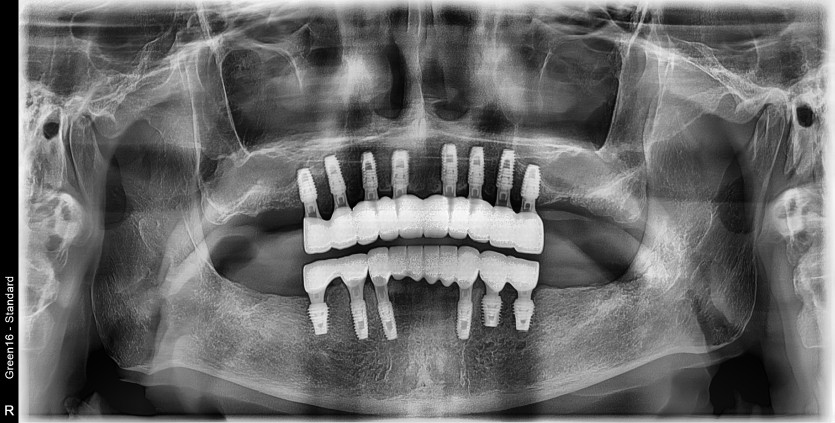

만 73세 전체 임플란트 중례

상, 하악 전체 임플란트 증례입니다.

14개의 임플란트로 완성하였습니다.